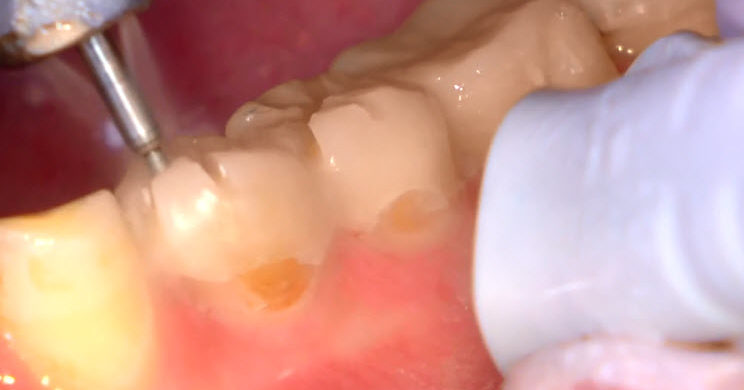

Préparations à travers le mock-up (vidéo)

Voici une vidéo présentant la méthode de préparations à travers un mock-up. Elle doivent être envisagées à l’aide de fraises spécifiques…

RC2-2018-Les préparations à travers le mock-up en vidéo 2 from Information dentaire on Vimeo.